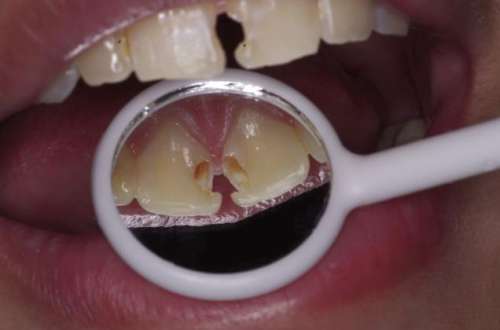

在進行隱形牙齒矯正之前,首先需要選擇一家好的牙科醫(yī)院就診。專業(yè)的牙科醫(yī)院和醫(yī)生是保障矯正成功與保護患者口腔健康的基石。好的醫(yī)院在矯正過程中不易出錯,保障矯正的效果和患者的口腔健康。